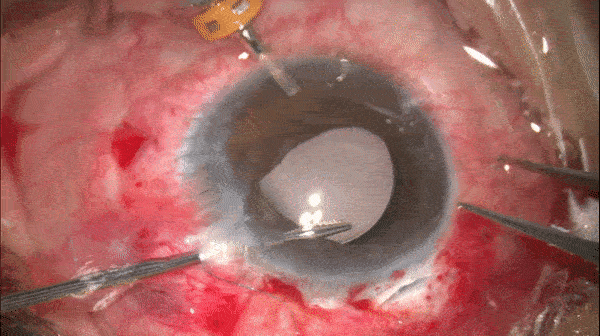

注入IOL并将另一侧晶体襻留置于眼外。

开睑器怎么用术说睛彩 | 金海鹰教授:使用8-0缝线的无巩膜瓣人工晶体固定手术_https://www.jmylbn.com_新闻资讯_第6张